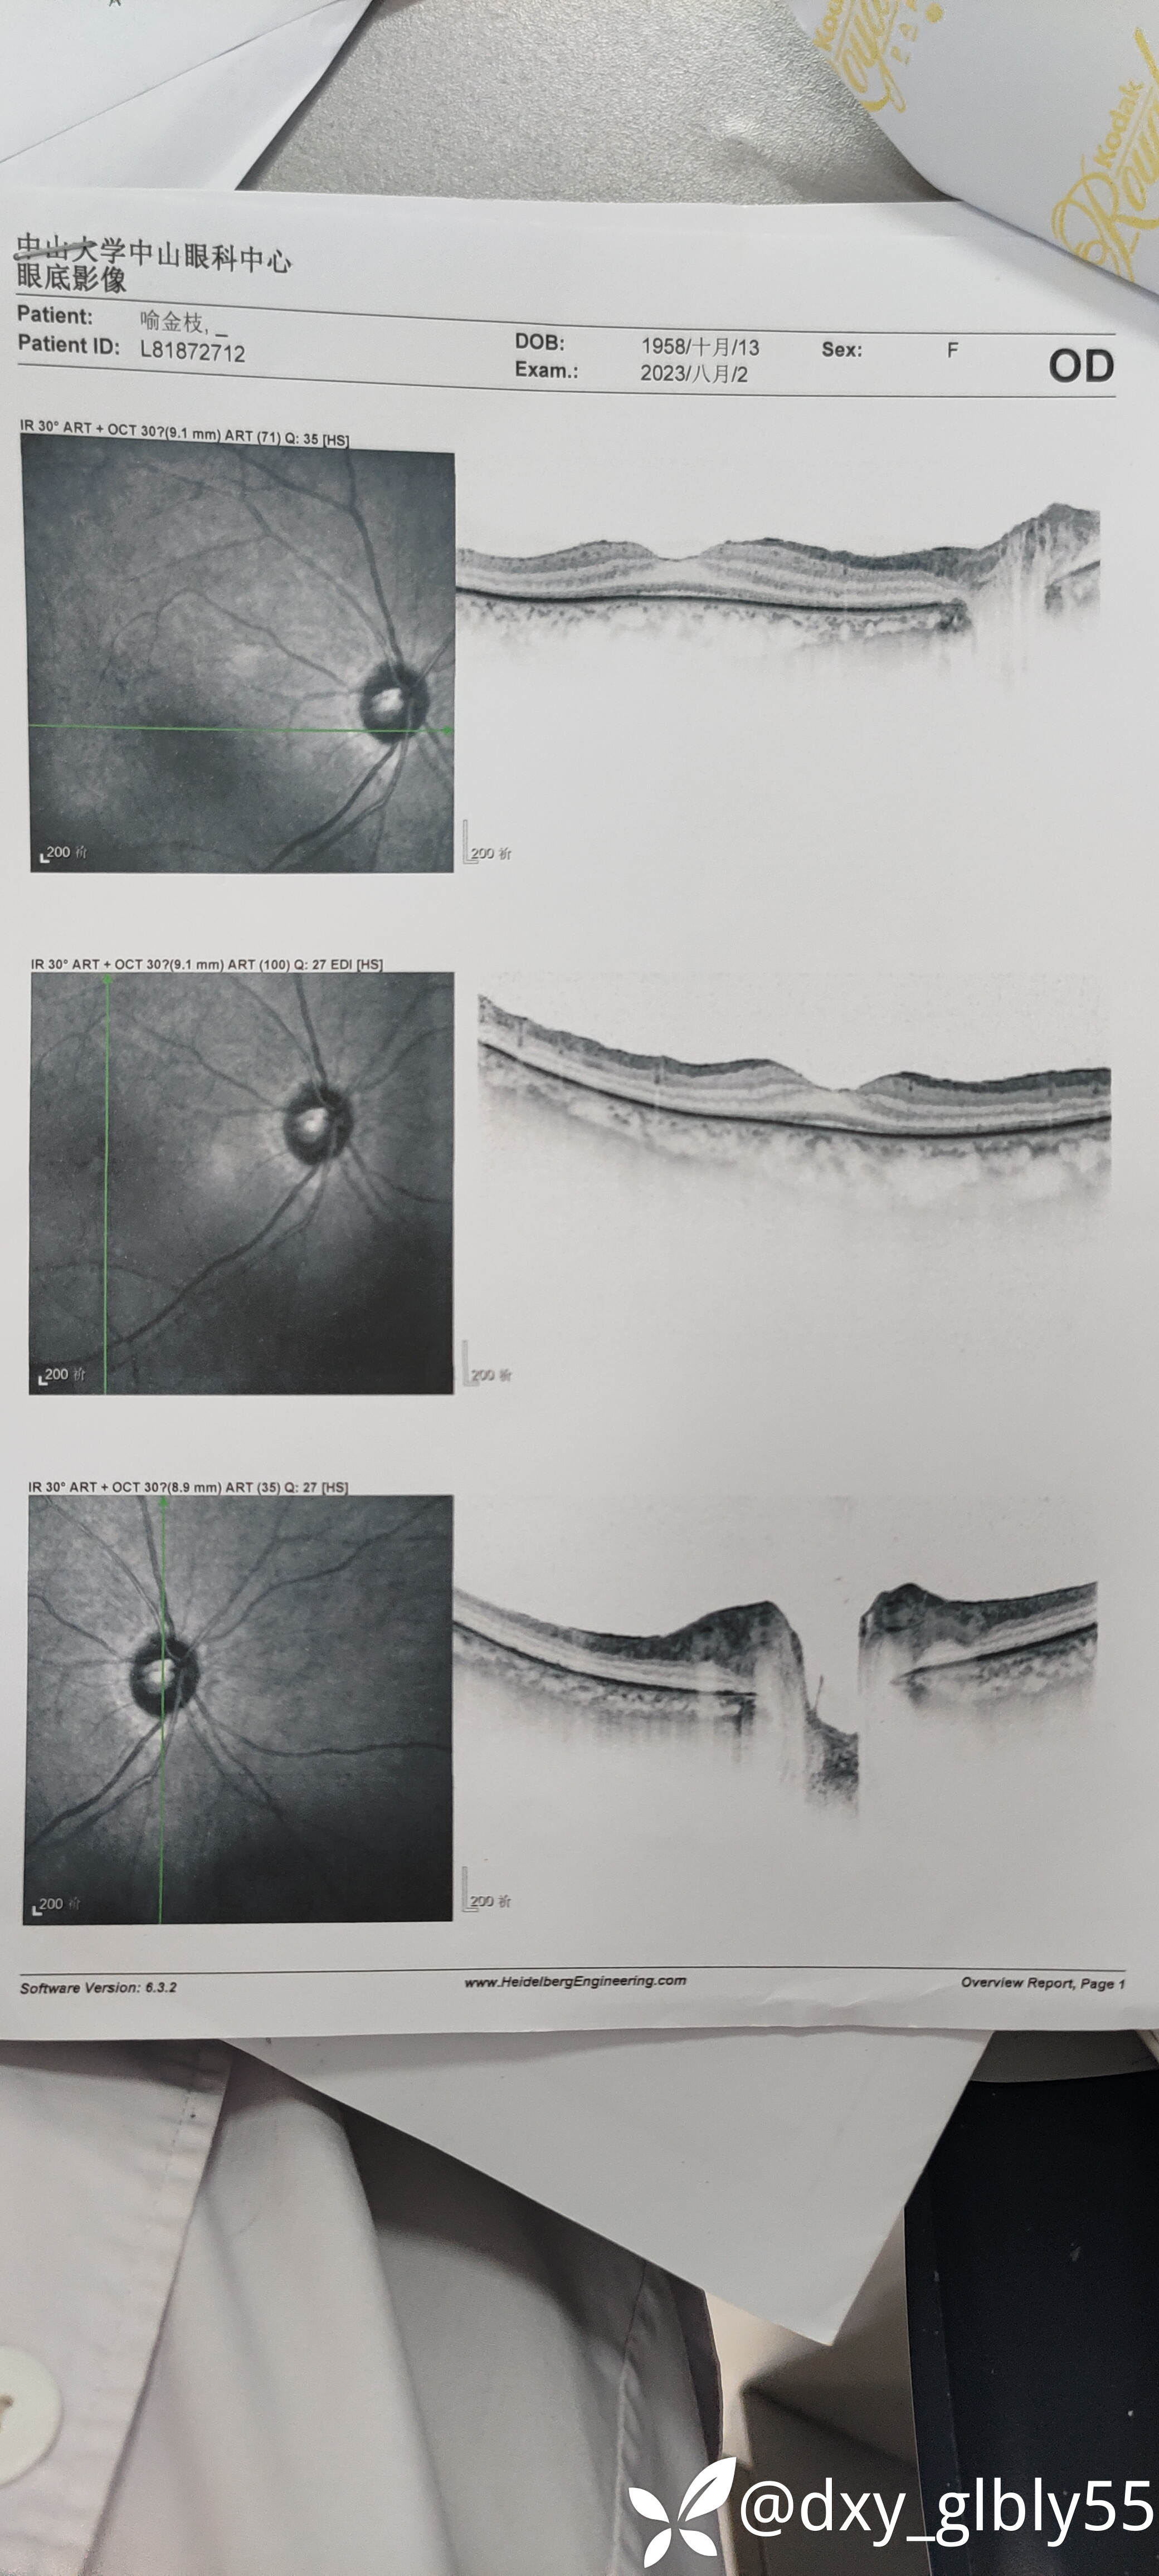

这个病人做完手术后因为效果没有达到她的期待,所以后续就没有怎么跟我联系,今年年初的时候患者因为视力下降的已经比较明显了,所以再次找到我,当时给她查的视力等专科情况vod:指数/1m vos:指数20/cm

就诊纪录以及一些有价值的特检结果我放在下面,除了电生理检查有异常在其他的特检没有表现明显的异常

一些特检结果我放在下面,请各位老师帮忙看一下,这个病人看了很多地方,很是苦恼